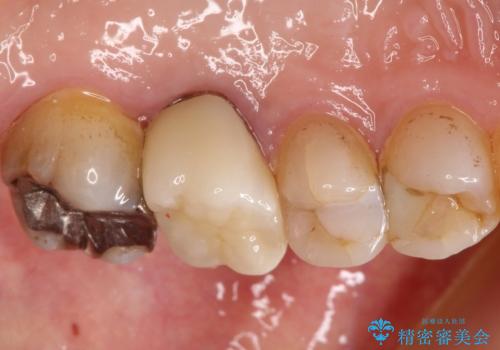

発見の難しい虫歯。根管治療から被せもの治療

- 定期検診にて被せものと歯との隙間に虫歯を発見した患者様です。

根管治療から被せもの治療(ベレッツァ)まで行いました。(根管治療は林院長に依頼)